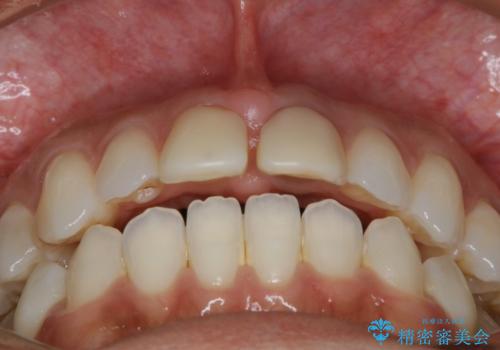

すきっ歯を治したい。インビザライン・ライトによる矯正治療

- 正中離開を気にされて来院された患者様です。

インビザラインでの治療を希望され、正中離開のみ治したいとのことだったので、インビザライン・ライト(片顎)での治療を選択しました。